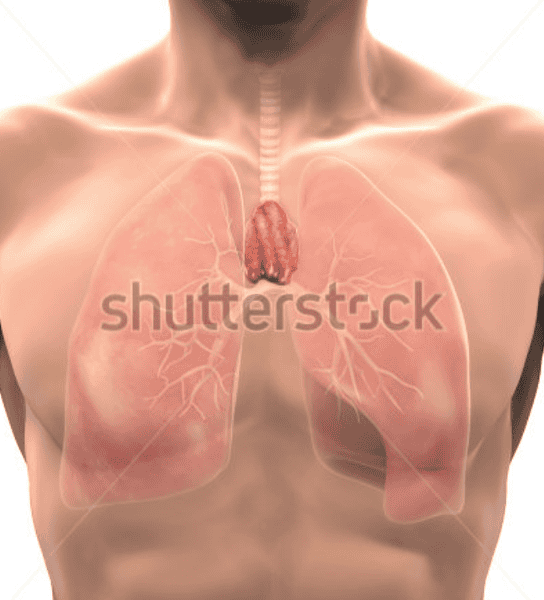

Thymus